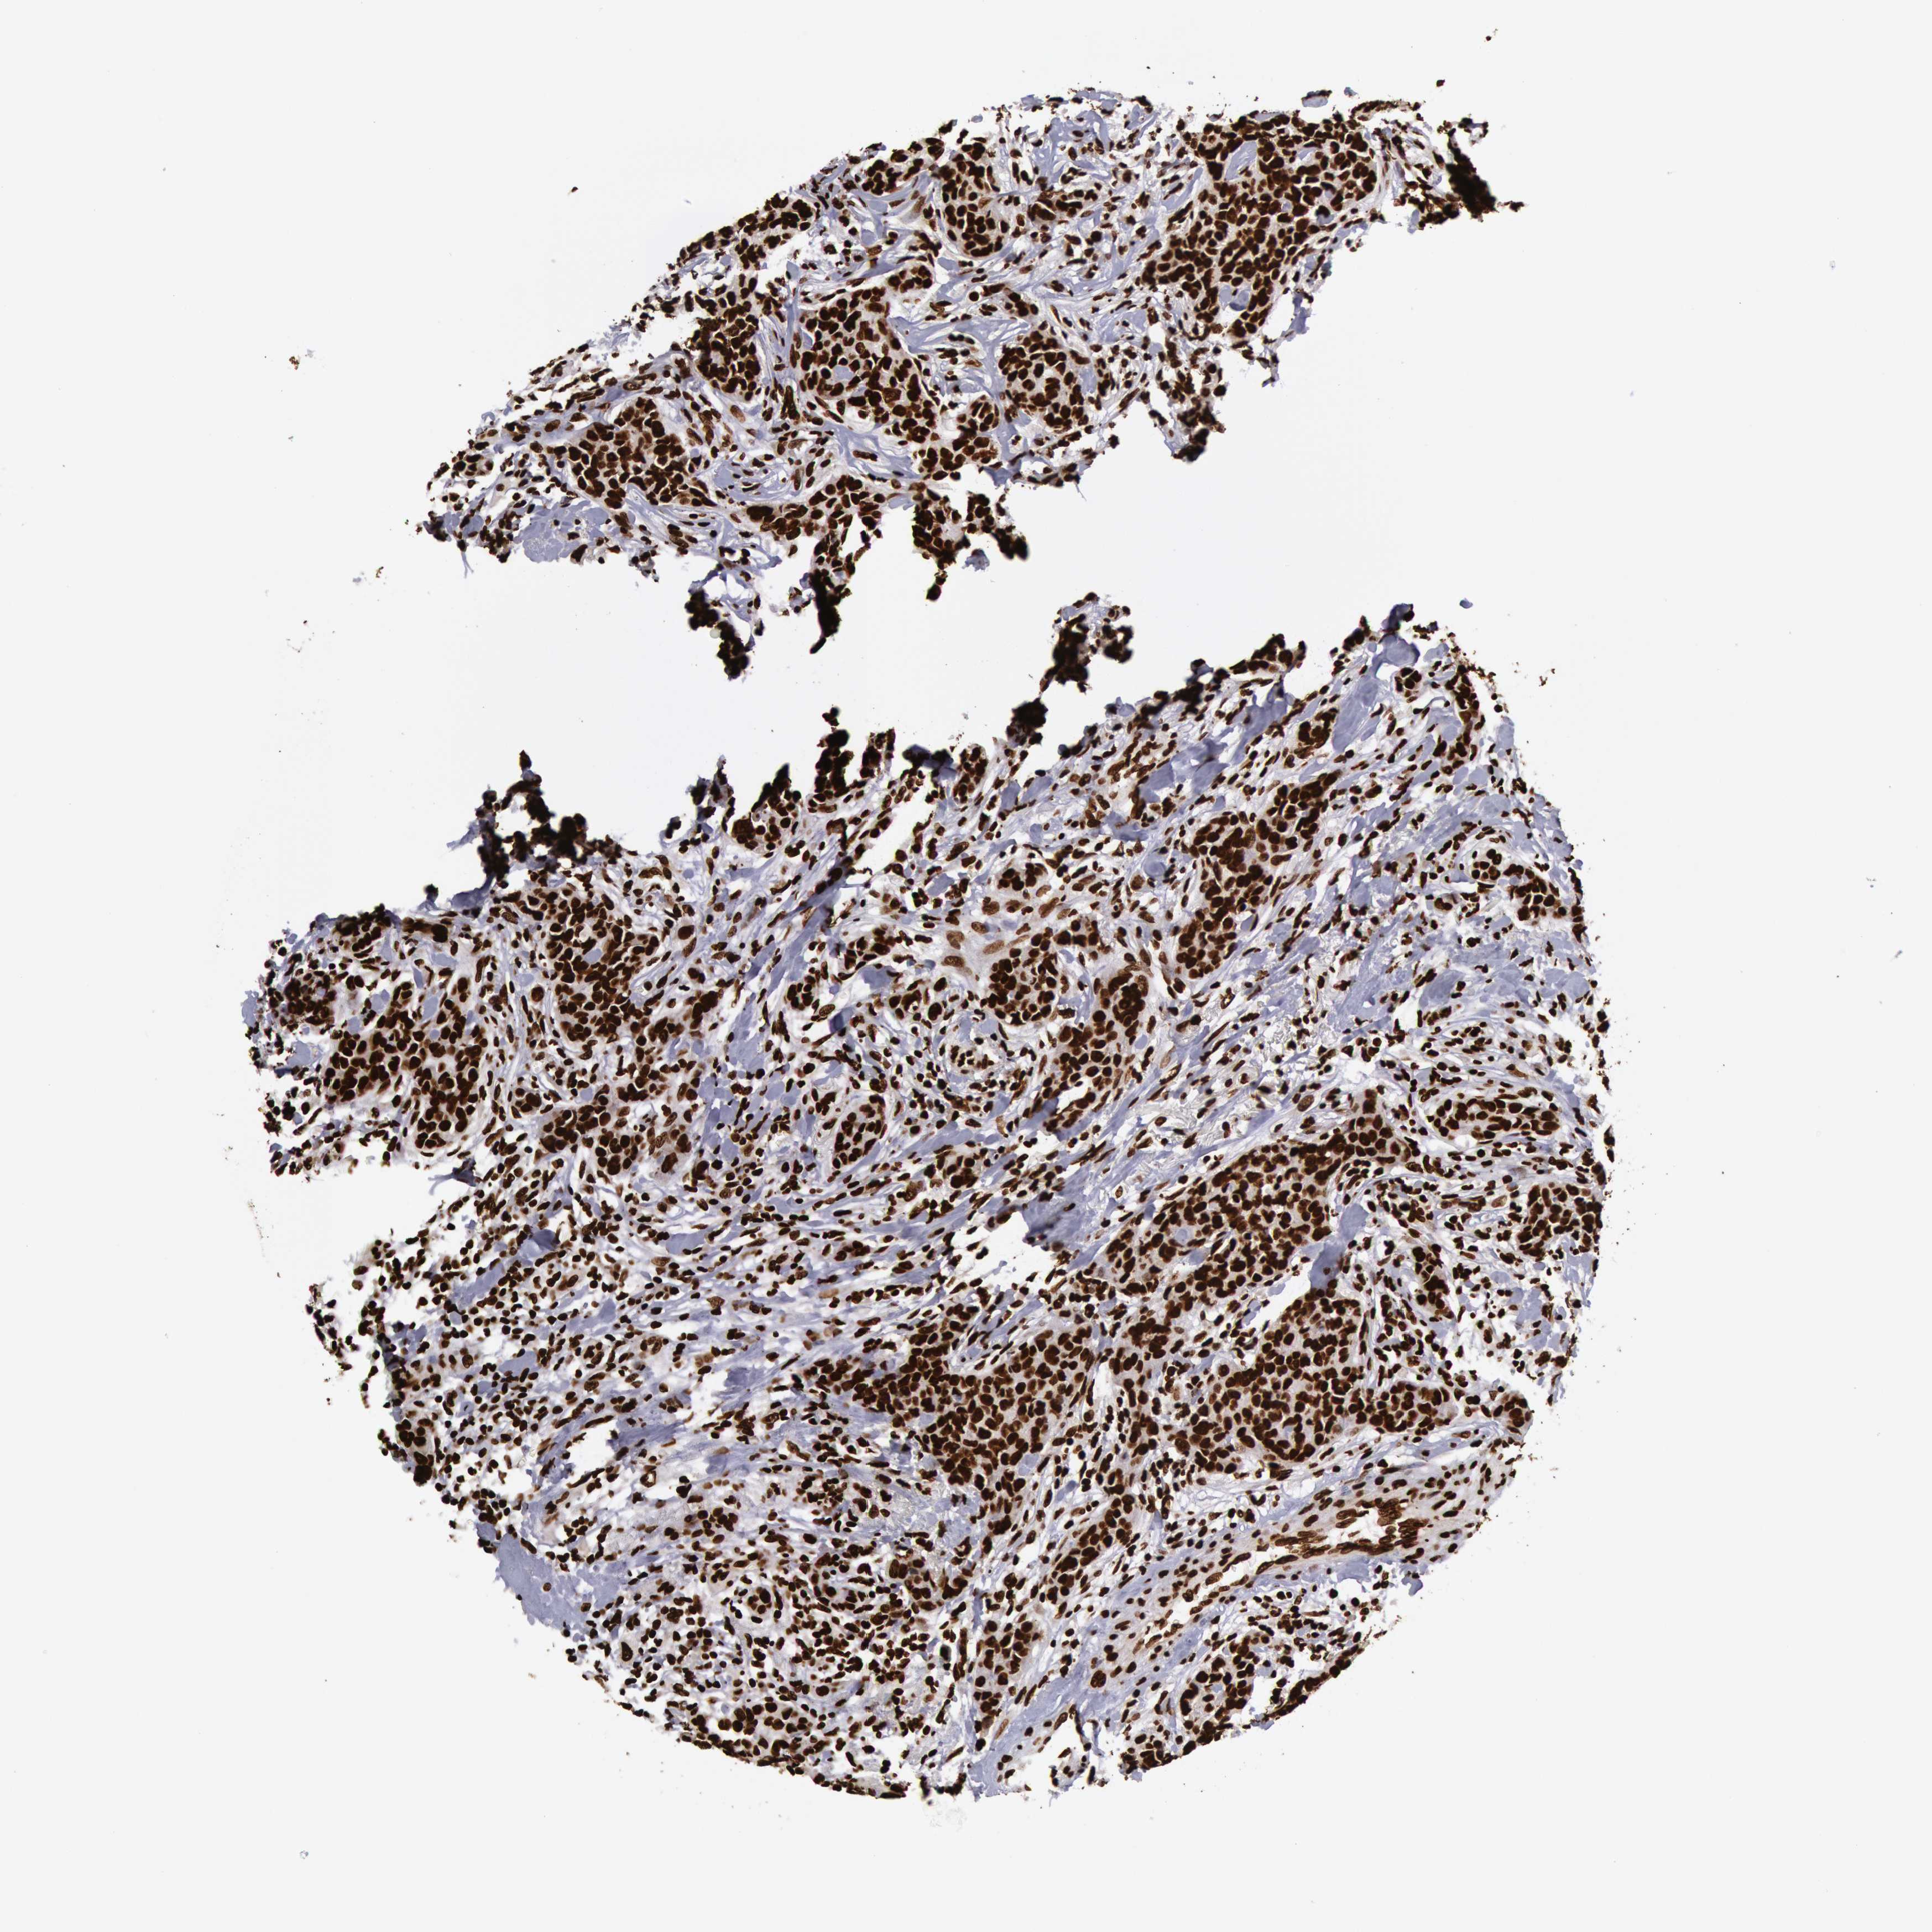

CANCER BREAST CANCER Show tissue menu

BRCA TCGA BRCA VALIDATION PROTEIN EXPRESSION